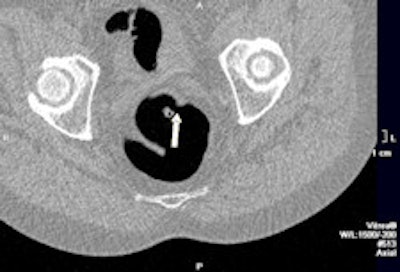

Example of a test case with two subtle rectal lesions in the rectum. Left: The small 7-mm polyp was detected by four out of five readers. Right: The 1-cm lesion with flat morphology was detected by all readers. This lesion was a flat cancer. Images courtesy of Dr. Philippe Lefere."The same radiographers were further evaluated in a larger study, also with good results," said co-author Dr. Philippe Lefere, a radiologist at Stedelijk Ziekenhuis in Roeselare, Belgium. "The program is conceived so that the novices perform the 75 examination themselves, and this allows them to learn the technique. We supervise each examination, and afterwards they are tested."